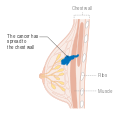

يمكن أن تؤدي الأورام الخبيثة إلى أورام نقيلية - أورام ثانوية (تنشأ من الورم الرئيسي) تنتشر إلى ما بعد مكان نشأتها. تعتمد الأعراض التي يسببها سرطان الثدي النقيلي على موقع الورم الخبيث. تشمل المواقع الشائعة للورم الخبيث العظام والكبد والرئة والمخ.[34] عندما يصل السرطان إلى مثل هذه الحالة الغازية، يتم تصنيفه على أنه سرطان من المرحلة الرابعة، وغالبًا ما تكون سرطانات هذه الحالة قاتلة.[35] تشمل الأعراض الشائعة لسرطان المرحلة الرابعة فقدان الوزن غير المبرر وآلام العظام والمفاصل واليرقان والأعراض العصبية. تسمى هذه الأعراض أعراض غير محددة لأنها يمكن أن تكون مظاهر لأمراض أخرى كثيرة.[36] نادرًا ما ينتشر سرطان الثدي إلى مواقع غير شائعة جدًا مثل العقد الليمفاوية المحيطة بالبنكرياس مما يؤدي إلى انسداد القنوات الصفراوية مما يؤدي إلى صعوبات في التشخيص.[37]

- المرحلة 4: هو السرطان "النقيلي" الذي له مآل أقل مواتاة لانتشاره خارج الثدي والغدد الليمفاوية الإقليمية.

- المرحلة 4، السرطان النقيلي (أي الذي ينتشر إلى أماكن أبعد)، مآله سيء، ويدار من خلال مجموعة متنوعة من جميع العلاجات الجراحية والإشعاعية والكيميائية والعلاجات المستهدفة. معدل البقاء على قيد الحياة لعشر سنوات يبلغ 5% بدون علاج و10% بالعلاج الأمثل.[171]